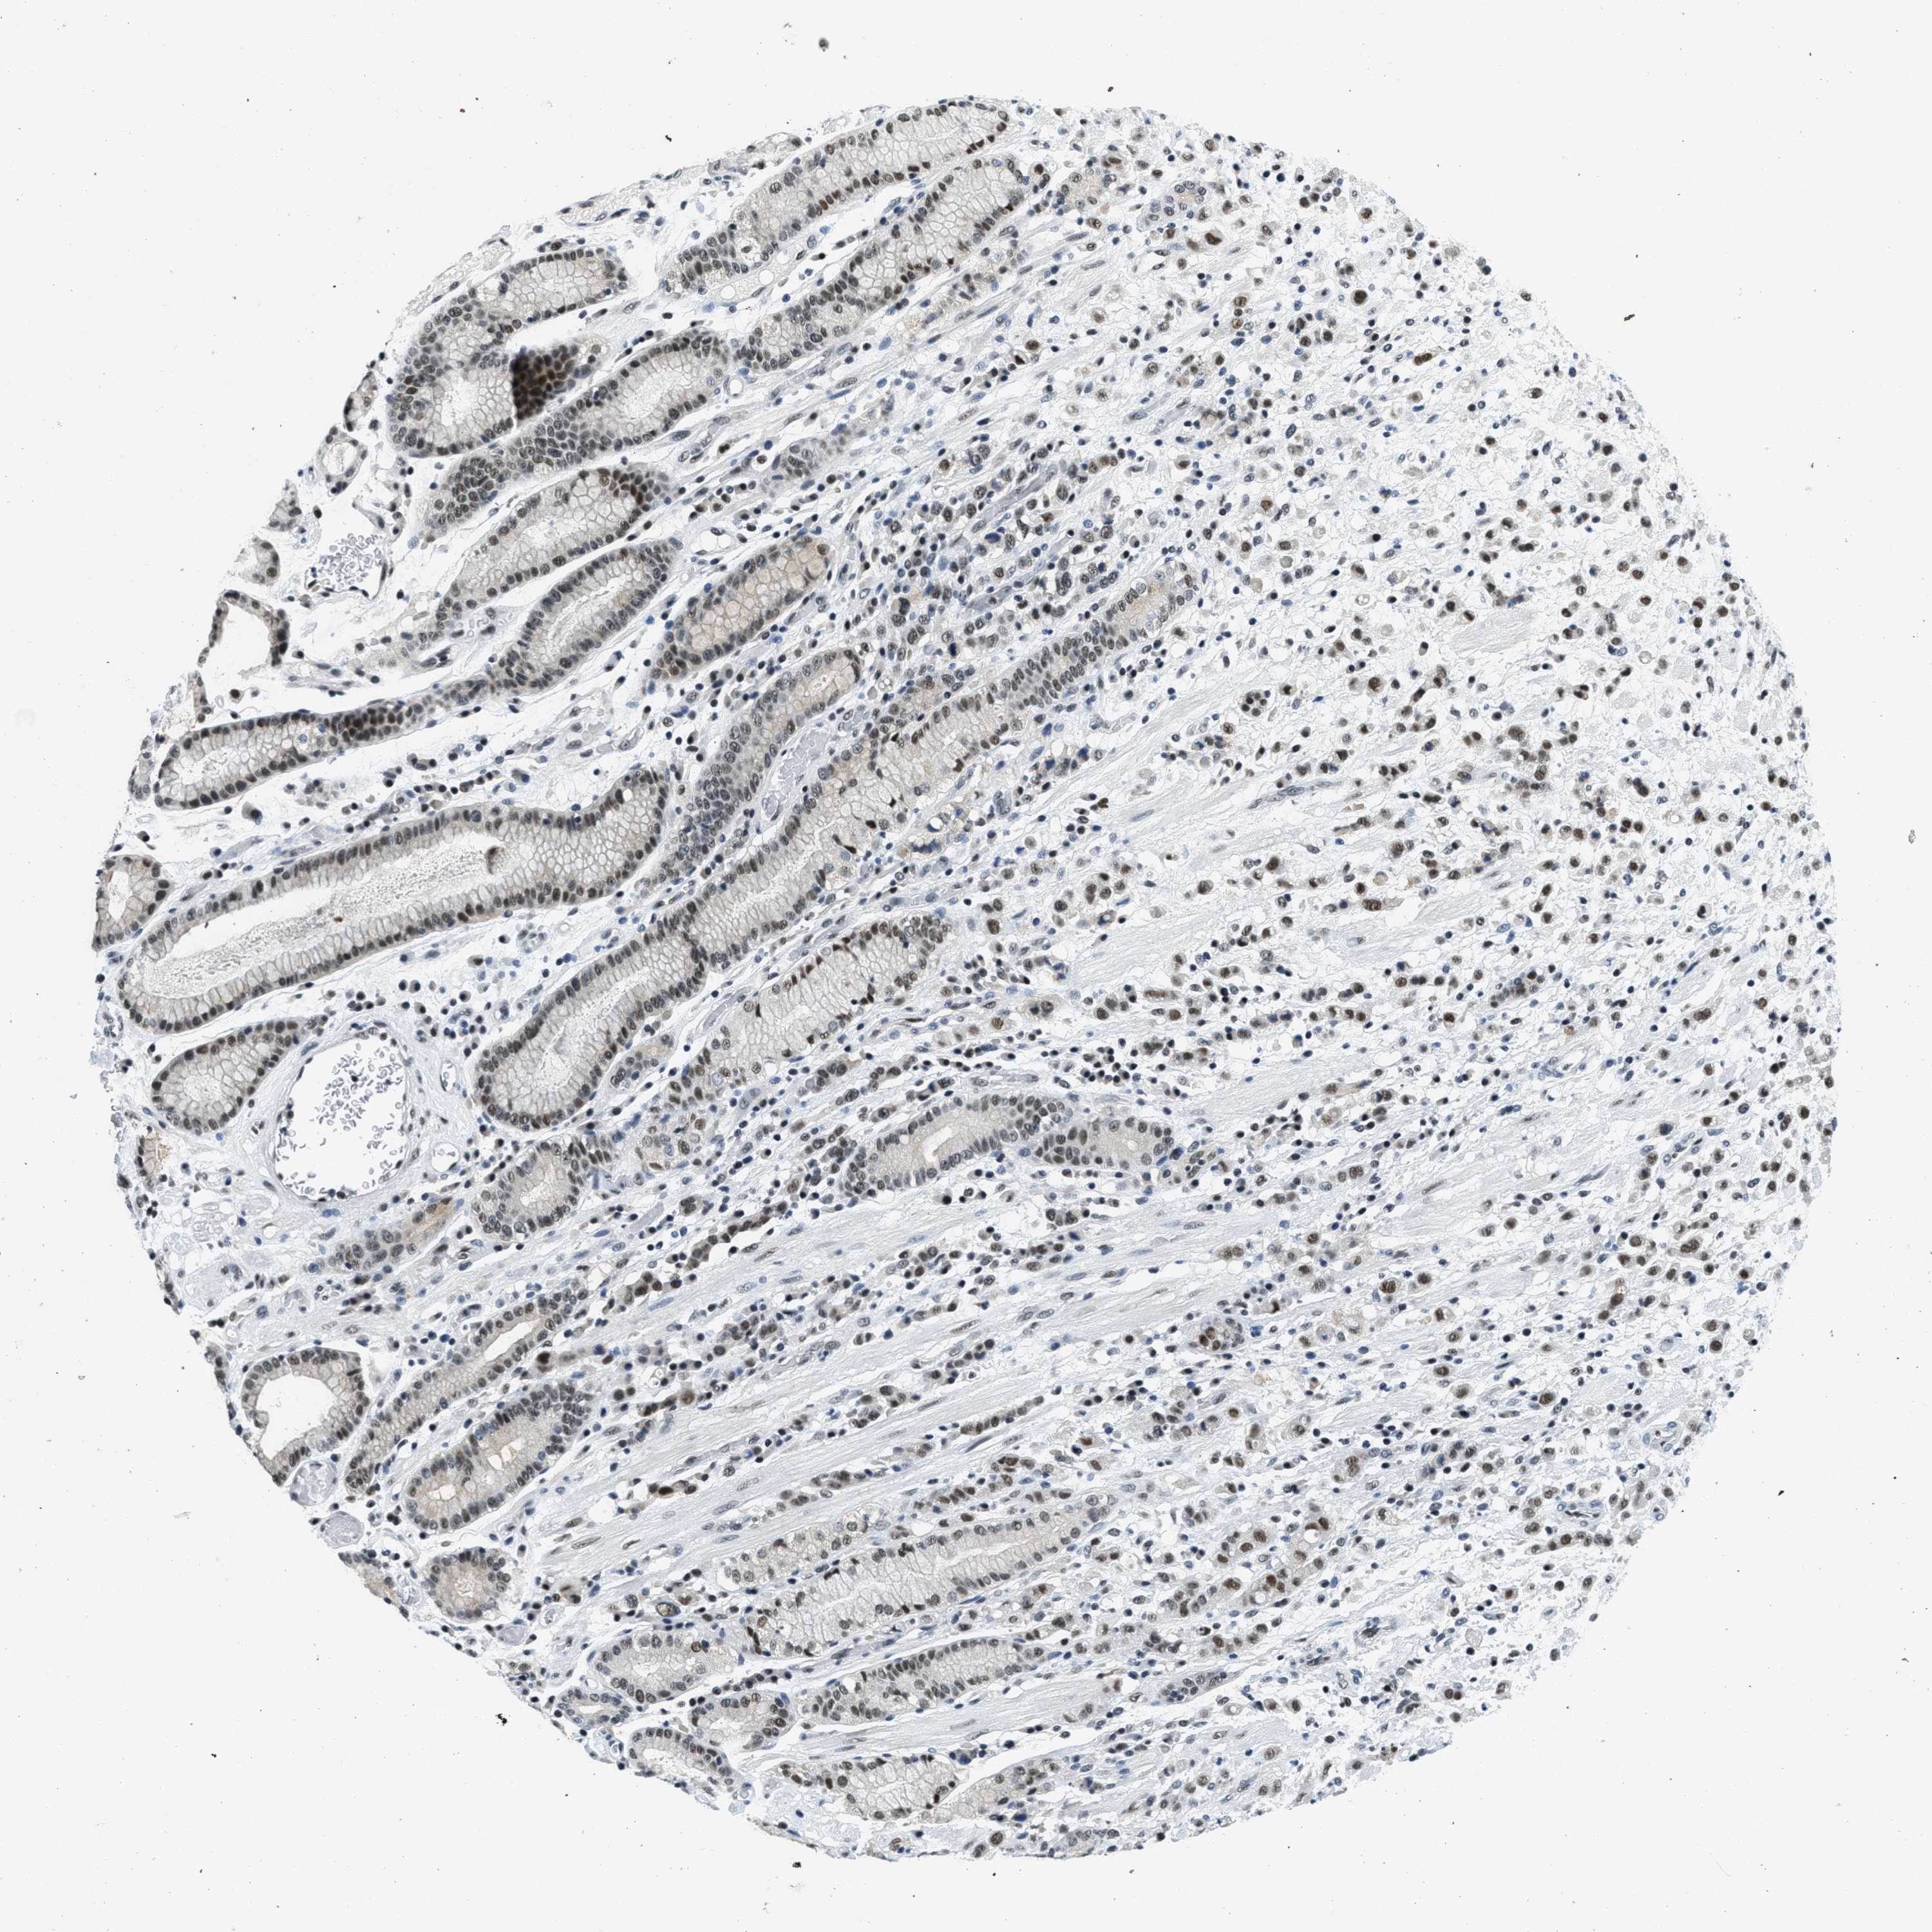

STOMACH CANCER - Protein expressioni

A mouse-over function shows sample information and annotation data. Click on an image to view it in a full screen mode. Samples can be filtered based on level of antibody staining by selecting one or several of the following categories: high, medium, low and not detected. The assay and annotation is described here.

Antibody stainingi

Antibody staining in the annotated cell types in the current human tissue is reported as not detected, low, medium, or high, based on conventional immunohistochemistry profiling in selected tissues. This score is based on the combination of the staining intensity and fraction of stained cells.

Each image is clickable and will lead to virtual microscopy that enables deeper exploration of all samples and also displays staining intensity scores, fraction scores and subcellular localization as well as patient and tissue information for each sample.

Antibody HPA017287

Antibody CAB004643

Staining

High

Medium

Low

Not detected

Intensity

Strong

Moderate

Weak

Negative

Quantity

>75%

75%-25%

<25%

None

Location

Nuclear

Cytoplasmic/membranous

Cytoplasmic/membranous,nuclear

Adenocarcinoma, NOS

Adenocarcinoma, High grade